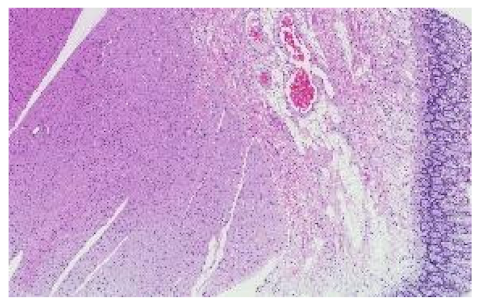

The preprocessing stage began with 66 WSI scans; we digitally cropped one region of interest (ROI) of size 1440 × 904 pixels for each tissue type in each slide. This resulted in three sets of images of 66 ROIs each, one set for the kidney, one for the skin, and one for the colon tissue. Cropping was used to minimize the presence of the non-tissue-related background, such as dust, hair, fibers, and other artifacts from previous preprocessing steps. The selected region coordinates were approximately the same within each tissue type. Each ROI was localized to cover an approximately sufficient area in each tissue type. Figure 3 shows samples of such ROIs for each tissue type amongst nine randomly chosen laboratories (three laboratories per tissue type).

Figure 3.

For illustration purposes, three ROIs from three laboratories per tissue type (column-wise). The first column is skin, the second column is kidney, and the last column is colon.